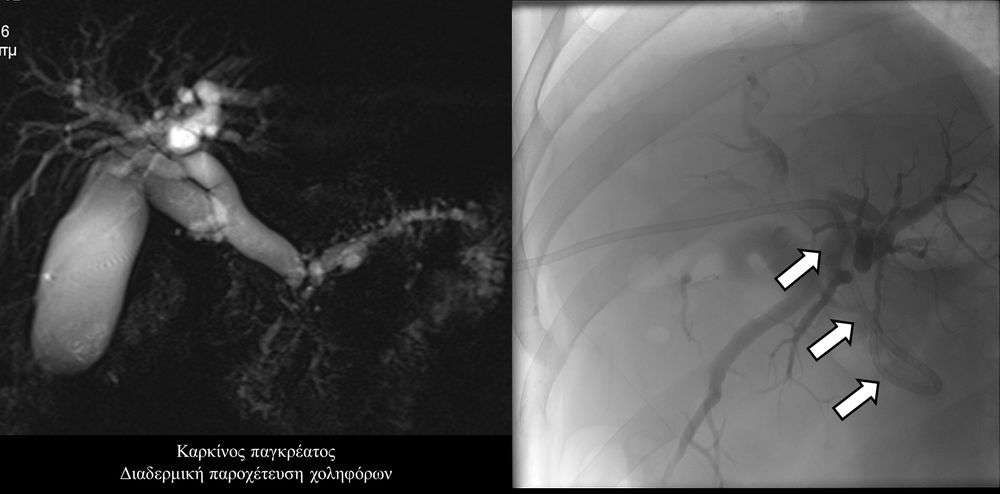

Σε πολλές περιπτώσεις πρωτοπαθών ή δευτεροπαθών όγκων ήπατος - παγκρέατος προκαλείται απόφραξη των χολαγγείων με συνοδό αποφρακτικό ίκτερο.Ο ασθενής με αποφρακτικό ίκτερο δεν μπορεί να υποβληθεί σε χημειοθεραπεία, αν δεν αποκατασταθεί ο ίκτερος με παροχέτευση των χοληφόρων.

Η παροχέτευση των χοληφόρων σε αυτές τις περιπτώσεις θα πρέπει να γίνεται άμεσα, είτε ταυτόχρονα προς τα έξω και προς το 12κτυλο (έσω-έξω παροχέτευση), είτε μόνο προς τα έξω με τη βοήθεια pigtailκαθετήρα (εξωτερική παροχέτευση)

Σε περιπτώσεις όπου υπάρχει απόφραξη των χοληφόρων και ενδείκνυται η τοποθέτηση ενδοπρόθεσης (stent), τότε η βατότητα των χολαγγείων και η αντιμετώπιση του αποφρακτικού ικτέρου μπορεί να διασφαλιστεί με την τοποθέτηση ενδοπροθέσεων (stents).